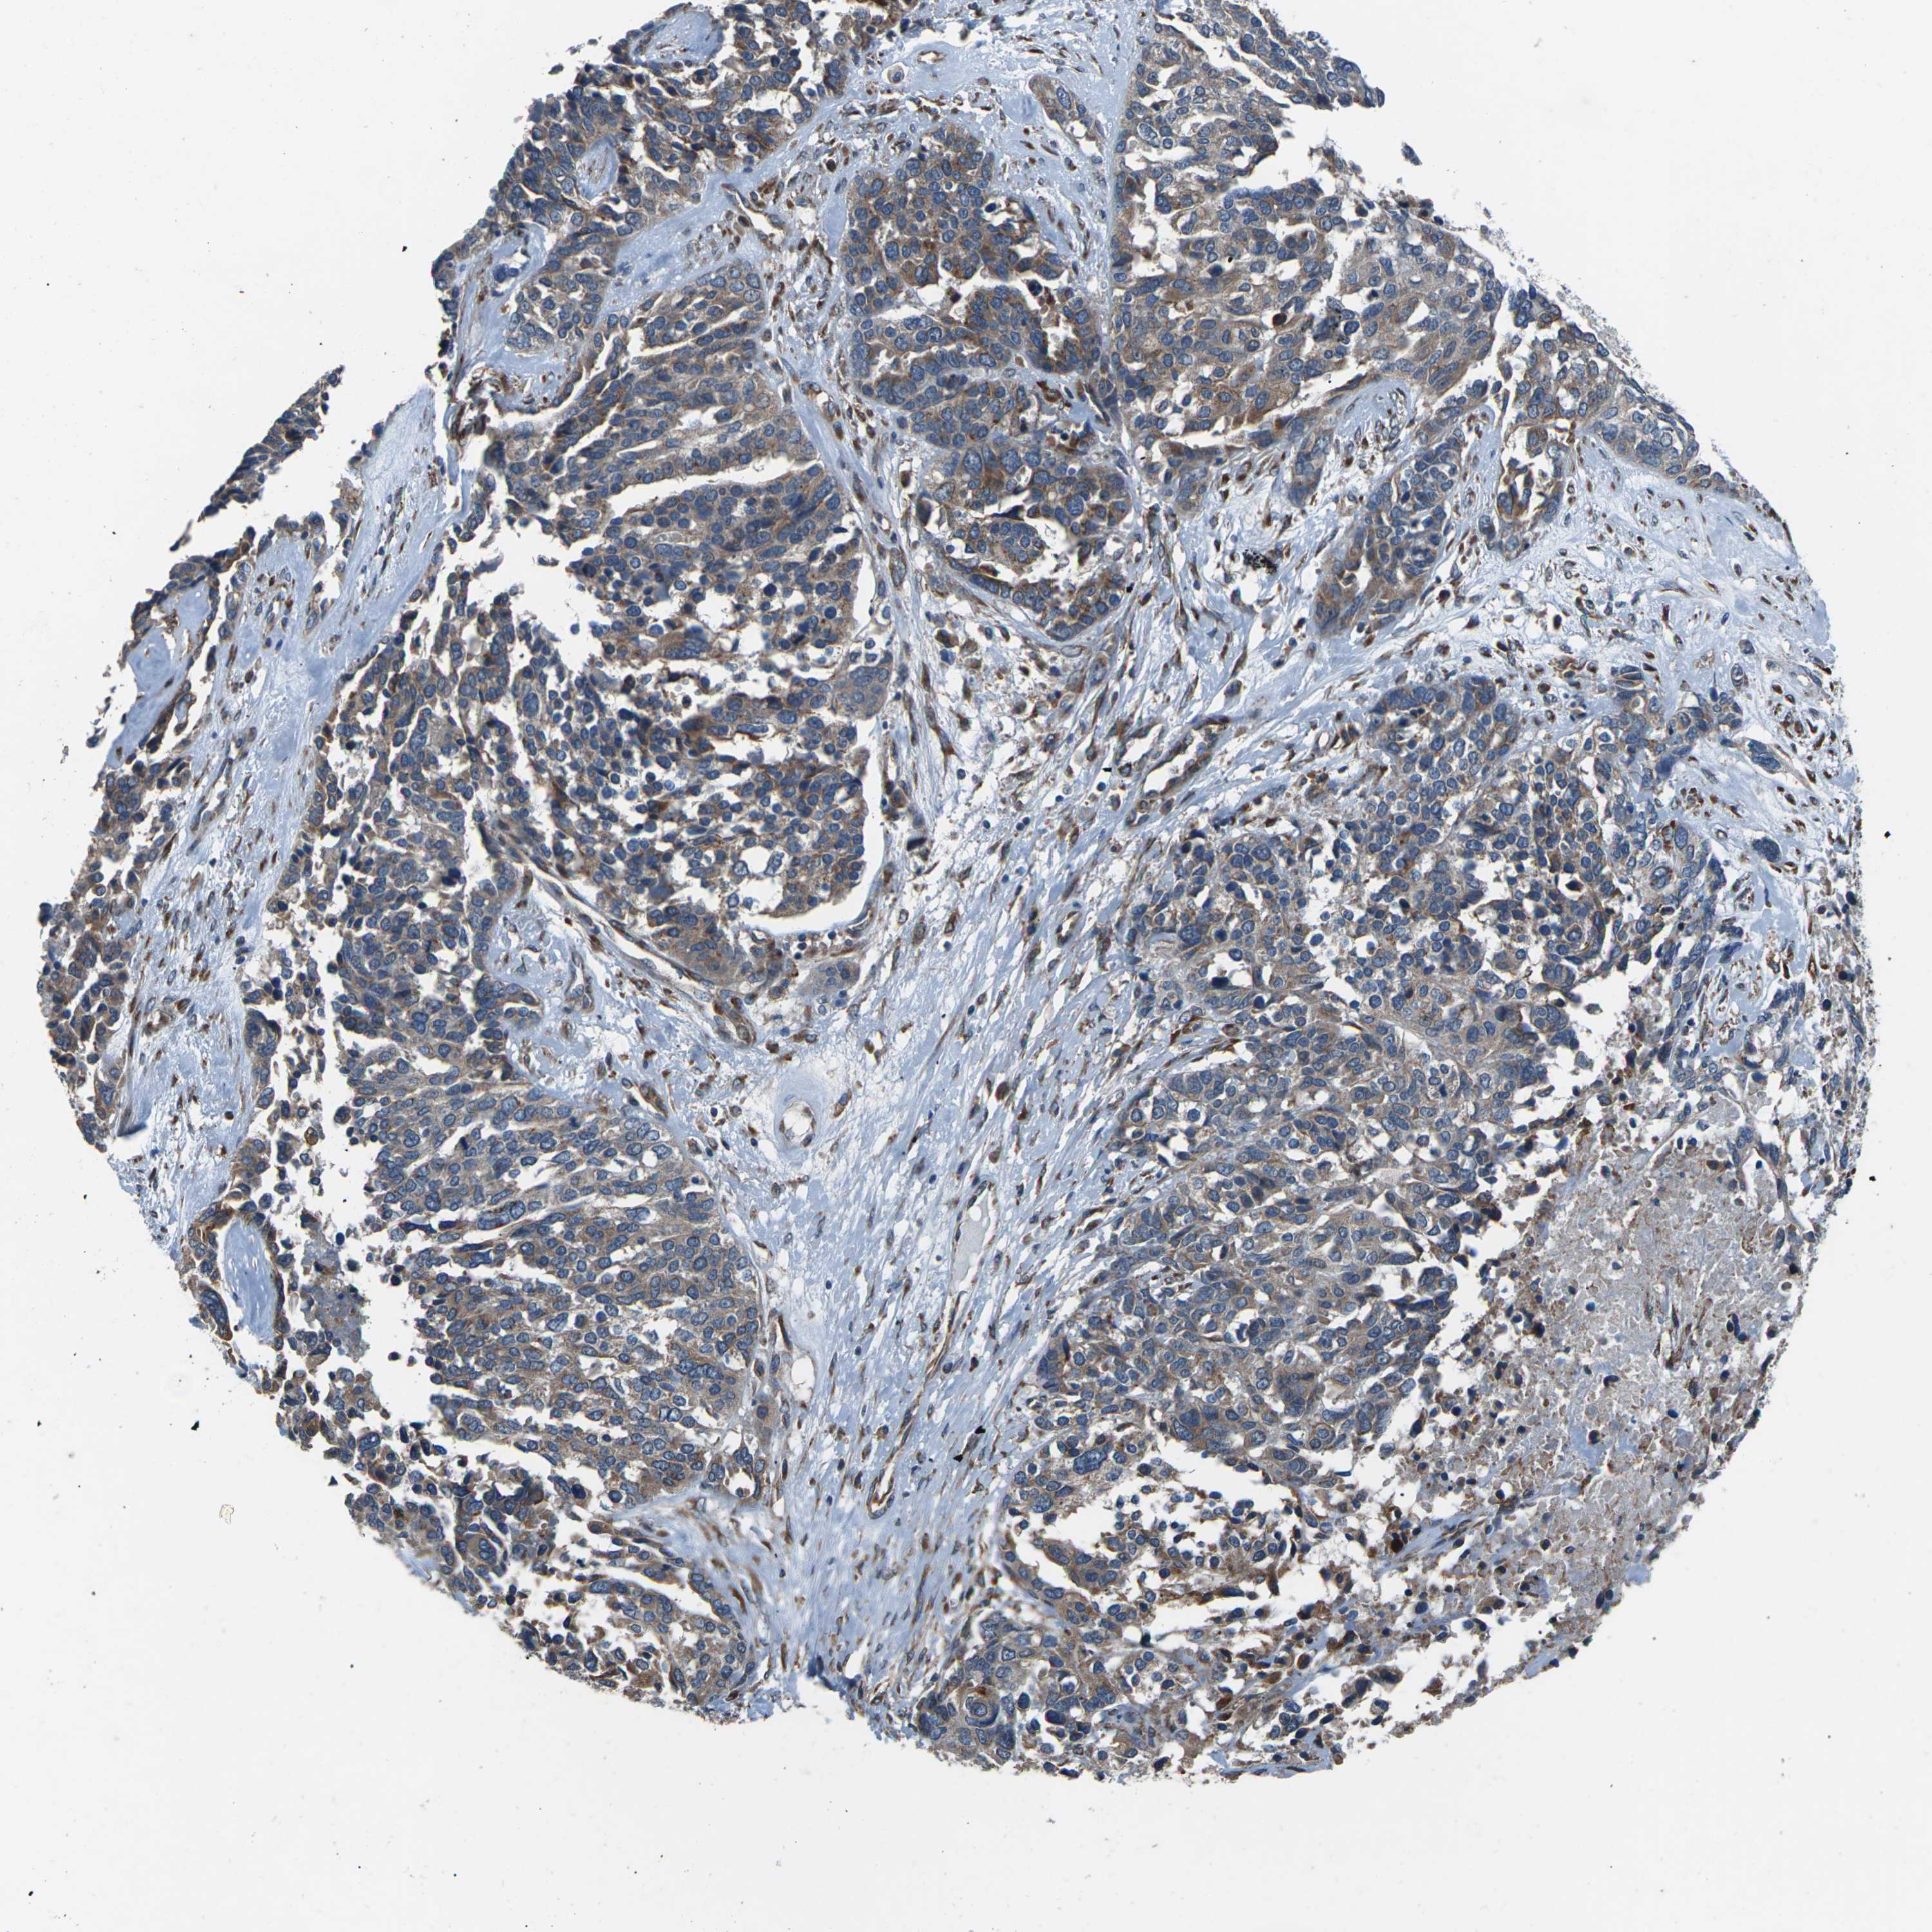

OVARIAN CANCER - Protein expressioni

A mouse-over function shows sample information and annotation data. Click on an image to view it in a full screen mode. Samples can be filtered based on level of antibody staining by selecting one or several of the following categories: high, medium, low and not detected. The assay and annotation is described here.

Note that samples used for immunohistochemistry by the Human Protein Atlas do not correspond to samples in the TCGA dataset.

Antibody stainingi

Antibody staining in the annotated cell types in the current human tissue is reported as not detected, low, medium, or high, based on conventional immunohistochemistry profiling in selected tissues. This score is based on the combination of the staining intensity and fraction of stained cells.

Each image is clickable and will lead to virtual microscopy that enables deeper exploration of all samples and also displays staining intensity scores, fraction scores and subcellular localization as well as patient and tissue information for each sample.

Antibody CAB014883

Staining

High

Medium

Low

Not detected

Intensity

Strong

Moderate

Weak

Negative

Quantity

>75%

75%-25%

<25%

None

Location

Nuclear

Cytoplasmic/membranous

Cytoplasmic/membranous,nuclear

Cystadenocarcinoma, serous, NOS

Carcinoma, endometroid

Cystadenocarcinoma, mucinous, NOS

Carcinoma, NOS